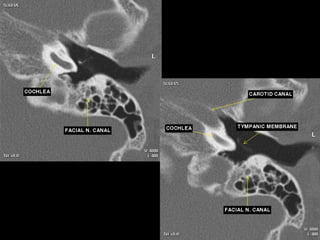

Facial nerve

 The facial nerve is one of the key cranial nerves with a complex and broad range of

functions.

 Although at first glance it is the motor nerve of facial expression which begins as a trunk

and emerges from the parotid gland as five branches it has taste and parasympathetic

fibres that relay in a complex manner.

 The facial nerve is the only cranial nerve that may show normal post-contrast

enhancement, although this applies only to the labyrinthine segment up to

the stylomastoid foramen. Enhancement of the other segments of the facial nerve and

other cranial nerves is considered pathologic.

Segments

 intracranial (cisternal) segment - zero branches

 meatal (canalicular) segment (internal auditory canal): 8 mm long, zero branches

 labyrinthine segment (IAC to geniculate ganglion): 3-4 mm long, 3 branches

(from geniculate ganglion)

 tympanic segment (from geniculate ganglion to pyramidal eminence): 8-11 mm

long, zero branches

 mastoid segment (from pyramidal eminence to stylomastoid foramen): 8-14 mm long, 3

branches

 extratemporal segment (from stylomastoid foramen to division into major branches): 15-

20 mm, 9 branches

Coronal temporomandibular joint level

 The horizontal carotid canal is seen as an

oval structure just

lateral to petrooccipital suture.

 The semicanal for the tensor tympani

muscle is seen as a small

lucency lateral to the carotid canal.

 The air-filled eustachian tube is inferior to

the tensor tympani,

and the TMJ is seen laterally

Geniculate ganglion level

 Tensor tympani muscle is seen

along the medial wall of the middle

ear, with the cochleariform process

separating it from the eustachian

tube below.

 The anteriormost part of the

cochlea is medial to the tensor

tympani.

 The geniculate ganglion is seen

as a small lucency superior to the

cochlea